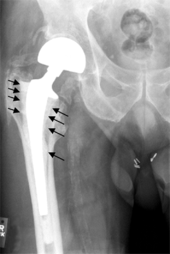

Fracture

Bones with internal fixation devices in situ are at risk of periprosthetic fractures at the end of the implant, an area of relative mechanical stress. Post-operative femoral fractures are graded by the Vancouver classification.